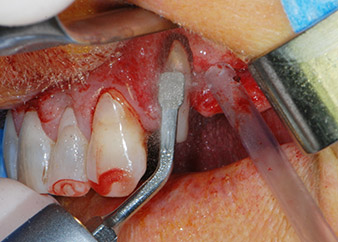

periodontium

Fig. 4: To preserve the tooth as a temporary abutment, the periodontium was debrided with piezoelectric equipment …

buccal apex of tooth 24

Fig 5: ... and the buccal apex of tooth 24 was abraded with the same instrument (apicoectomy).

However, we maintained our initial plan to retain both teeth as temporary bridge abutments during the six-months osseointegration period of the implants. At reentry, the situation would have to be reassessed. First, in an attempt to manage the endo-perio problem, the remaining root surface was carefully debrided with piezoelectric equipment (Piezomed, W&H, used with the spatula-shaped insert S1, originally designed for erosion of the lateral sinus wall) (Fig. 4).

Then the apex was abraded with the same instrument to remove residual infected apical tissue and to reduce possible accessory root-canal ramifications (apicoectomy) (Fig. 5). A retrograde filling was not necessary because the orthograde filling had just been revised.